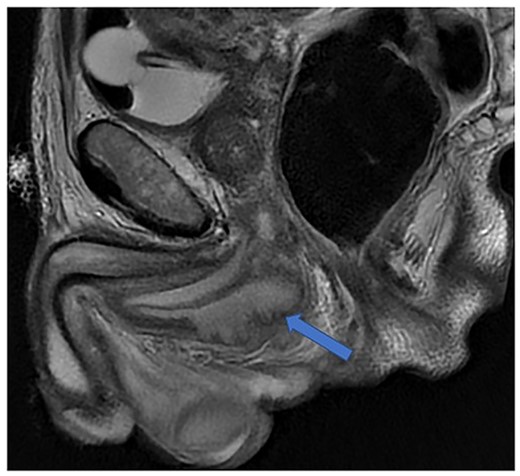

The patient was reviewed again a week later. On examination, a tender perineal mass extending into his posterior scrotum had developed. Again, there were no perianal skin abnormalities on examination. He was put on intravenous antibiotics, and a repeat MRI of his pelvis was organized. This revealed a persistent perineal collection, in proximity with, but not involving, the external anal sphincter, as well as the bulbar urethra and scrotum (Fig. 4).

Case 2: coronal and axial T2-weighted images demonstrating the collection (red and green arrows) significantly compressing the urethra and corpus spongiosum (yellow arrow) to the right of the midline, and close to, but not involving, the anal sphincter (blue arrow).